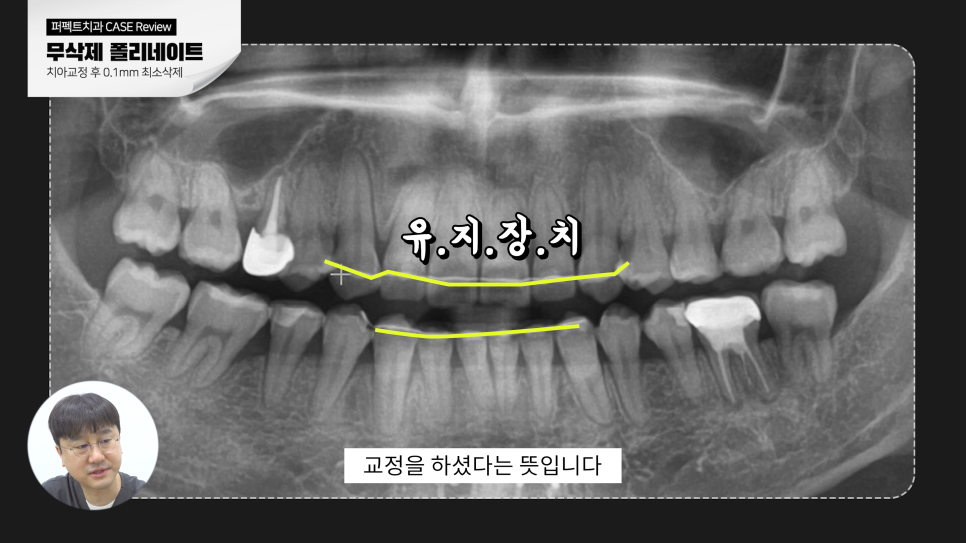

환자분은 이전에 교정치료를 받은 경험이 있어 유지장치를 부착하고 있었고

치아는 교정되어 가지런한 상태를 잘 유지되어 있었습니다.

덕분에 폴리싱하거나 0.1mm 정도 최소삭제로 진행할 수 있게 되었고